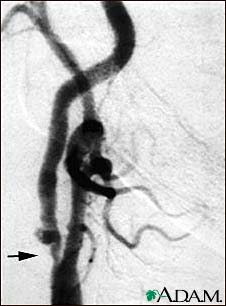

- Heart problems, such as a heart attack or abnormal heart beat

- Stroke

- Bleeding inside the body

- Shock (extreme drop in blood pressure)

If any of these serious disorders are present, you will usually also have symptoms like chest pain, a feeling of a racing heart, loss of speech, change in vision, or other symptoms.